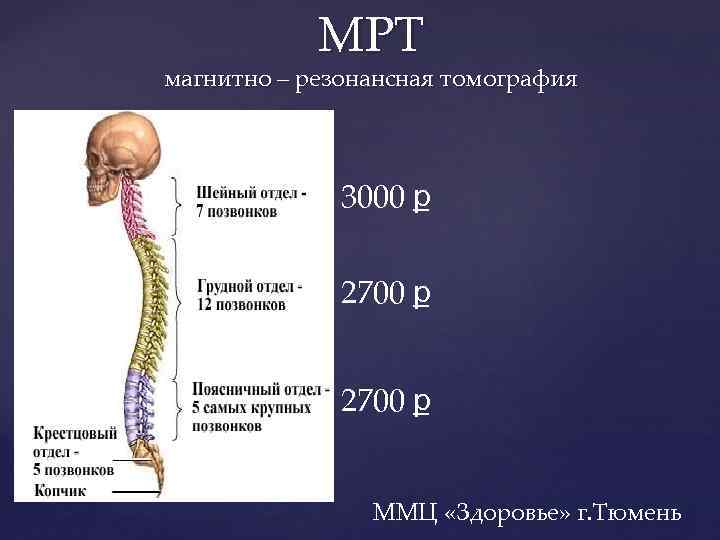

Отделы позвоночника для мрт схема фото и названия